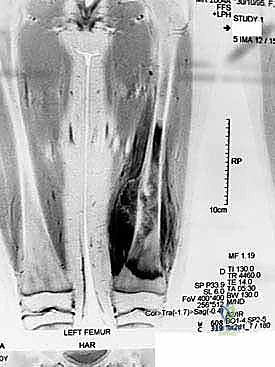

- التصوير بالرنين المغناطيسي (MRI): يوفر صوراً مفصلة للغاية للأنسجة الرخوة المحيطة بالعظم (العضلات، الأوعية الدموية، الأعصاب) ويحدد الامتداد الدقيق للورم داخل نخاع العظم وخارجه، وهو أمر حاسم لتخطيط الجراحة.